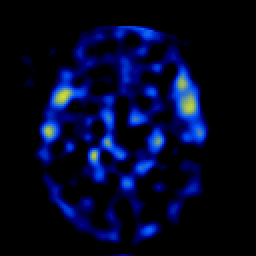

SPECT TL Study #4 -- Slice #26